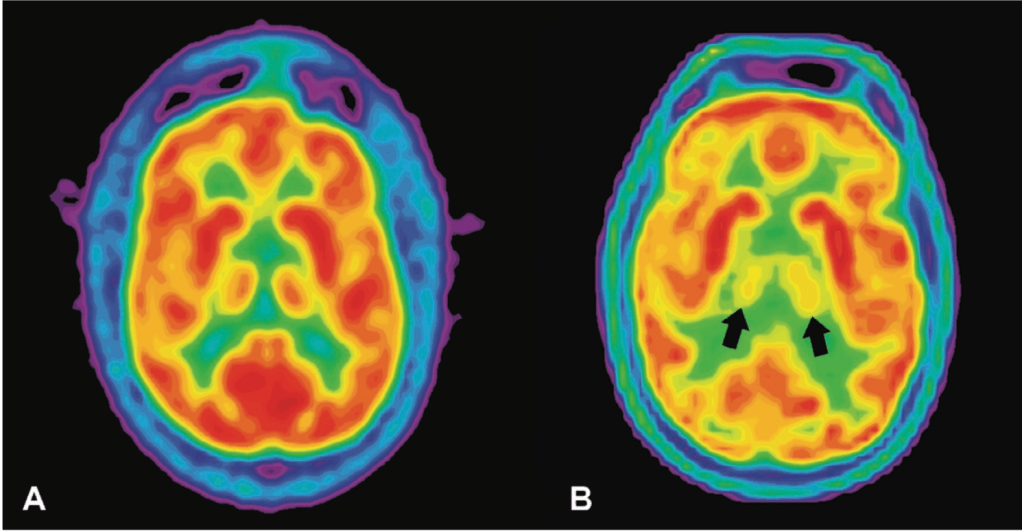

This idea of clumped proteins may make you think of another common neurodegenerative disease – Alzheimer’s disease – where at least part of the dementia is thought to be caused by inappropriate clumps of proteins that are toxic to neurons and lead to their destruction, especially in the parts of the brain important for memory. Alzheimer’s disease is not categorized as a prion disease, however, because the effects are not mediated by the same prion protein. Nonetheless, FFI works similarly – clumps of proteins are found particularly in an area of the brain called the thalamus, which has many functions that will be discussed in subsequent sections [1]. The clumps of prion protein lead to the total destruction of neurons in this brain area, which contributes to most of the symptoms described above.

The major hallmark of FFI is the total degeneration of the thalamus. Located in the center of the human brain, the thalamus is the major hub that routes incoming sensory information to destinations all over the brain, especially to the cerebral cortex. Due to its super interconnected nature with other parts of the brain, a healthy thalamus is implicated in many different types of perception and behavior. Destruction of the thalamus can therefore lead to movement and thought dysfunction, as well as autonomic dysfunction, probably through its connections with the nearby hypothalamus. Importantly for understanding FFI, the thalamus has also been implicated in sleep and wakefulness cycles by coordinating the large-scale waves of electrical activity that travel across the brain and are indicative of sleep [11,12]. Interestingly, stroke damage to the thalamus can cause permanent coma, while prion damage in the thalamus in FFI leads to persistent wakefulness. But what is so important about sleep that its absence would lead to death?

Thus far, scientists have been able to identify a variety of vital roles sleep plays in maintaining our physical and mental well-being. It is thought that during sleep, toxins that have built up in the brain throughout the day are removed and memories are consolidated for future use [13]. Sleep cycles through a variety of stages each night that each exhibit specific brain activity (for a detailed look at sleep stages, check out these previous NeuWriteSD articles). Deep, restorative, slow wave sleep transitions to REM (rapid eye movement) sleep, which is when we mostly experience dreaming. Patients with FFI first lose the ability to enter slow wave sleep, and eventually experience the loss of REM sleep. When electroencephalography (EEG) is used to examine electrical activity in the brains of healthy and FFI patients via electrodes placed on the scalp during sleep, FFI patients do not show any of the expected brain waves controlled by the thalamus that signify sleep. In fact, their brain activity is not consistent with wakefulness either, leaving patients in a persistent state somewhere between wake and sleep. Further into disease progression, any lapse into a REM-like state that does occur becomes unlinked from sleep, leaving patients in a stupor and acting out waking dreams at any point in the day [14].